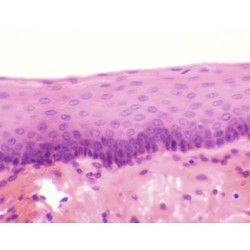

Histologia